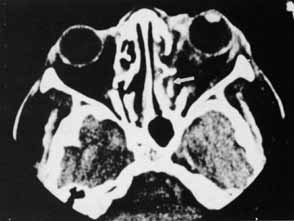

Hemorrhage can be localized to the subperiosteal potential space, extraconally, or intraconally within the orbital soft tissue, or within the belly of extraocular muscles. The condition can be associated with pain, nausea, diplopia, or decreased vision. The more obvious finding might be lid ecchymosis and edema but requires further examination for retroseptal signs. There may be conjunctival chemosis or expanding ecchymosis. Clinical findings reflect the mass effect of accumulating blood within the confines of the bony orbit and orbital septum (Fig. 2). Subperiosteal hematomas are usually restricted by the tight adherence of the periosteum to the orbital bone except in areas, such as suture sites, where this association is weakest. Hemorrhage localized to the muscle sheath may cause selective extraocular muscle restriction that requires radiologic studies to distinguish it from incarceration into a fracture site (Fig. 3). Localized bleeds within the orbital soft tissue can produce proptosis or dystopia. Diffuse hemorrhage may limit eye movement globally and increase retropulsive resistance. Increased intraorbital pressure on the globe and optic nerve may cause elevated intraocular pressure, choroidal folds, compressive retinal vascular compromise, or optic neuropathy, so maintaining vigilance for progressive, potential, vision-threatening situations is important.

Fig. 3 CT scan of inferior orbital hematoma (X) involving the inferior rectus muscle and causing severe upgaze and moderate downgaze limitation.